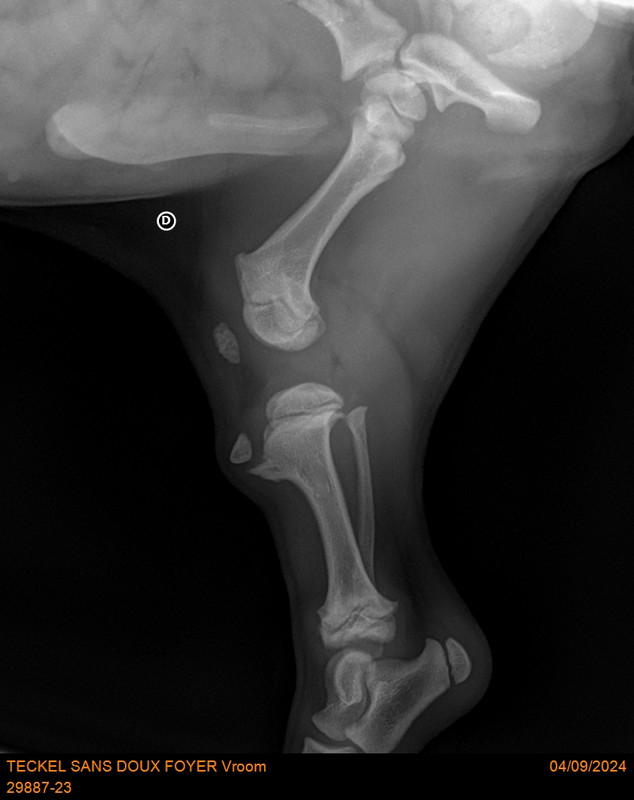

[Image: 29887-23-TECKEL-SANS-DOUX-FOYER-Vroom-20788.jpg]

[Image: 29887-23-TECKEL-SANS-DOUX-FOYER-Vroom-20789.jpg]

[Image: 29887-23-TECKEL-SANS-DOUX-FOYER-Vroom-20790.jpg]

Patte arrière gauche [Image: chien-2010-32.gif]

Sur la deuxième radios les 2 cotés ne sont pas identiques. C’est là le problème ?

Oui, son problème de rotule au genou se répercute sur la hanche, d’où la nécessité de l'opérer de toute urgence sinon il risque une dysplasie de la hanche. Et aussi ne pas grandir normalement !